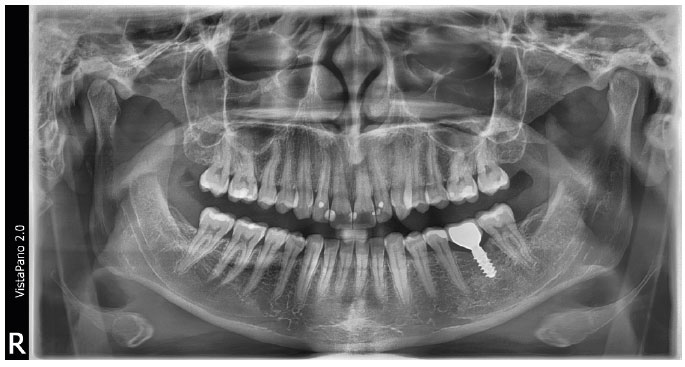

Das VistaPano S 2.0 von Dürr Dental ist ein hochmodernes digitales 2D-Panoramaröntgensystem, das durch innovative Technologien, intuitive Bedienung und höchste Bildqualität überzeugt. Die Kombination aus S-Pan-Technologie, modernem CsI-Sensor und VistaSoft AI sorgt für präzise Diagnosen, optimierte Arbeitsabläufe und eine deutliche Zeitersparnis im Praxisalltag. Dank kompakter Bauweise, schneller Aufnahmezeiten und intelligenter Automatisierung ist das System ideal für zukunftsorientierte Zahnarztpraxen.

Die S-Pan-Technologie analysiert automatisch mehrere Bildebenen und wählt die anatomisch relevantesten Bereiche aus. Dadurch entsteht ein besonders scharfes und individuell angepasstes Panoramabild. Selbst bei leichten Fehlpositionierungen werden verwertbare Ergebnisse erzielt – das reduziert Wiederholungsaufnahmen und erhöht die Diagnosesicherheit.